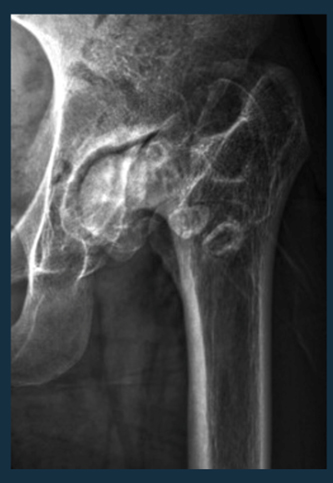

• İleri Evre (4. Evre):

–  İleri evrelerde, kalça eklemi ciddi şekilde hasar görmüş olabilir ve ağrı çok daha      şiddetli olabilir.

–  Cerrahi müdahale düşünülebilir. Total kalça protezi (THA) cerrahisi, kalça eklemi kireçlenmesinin ileri evrelerinde altın standarttır.